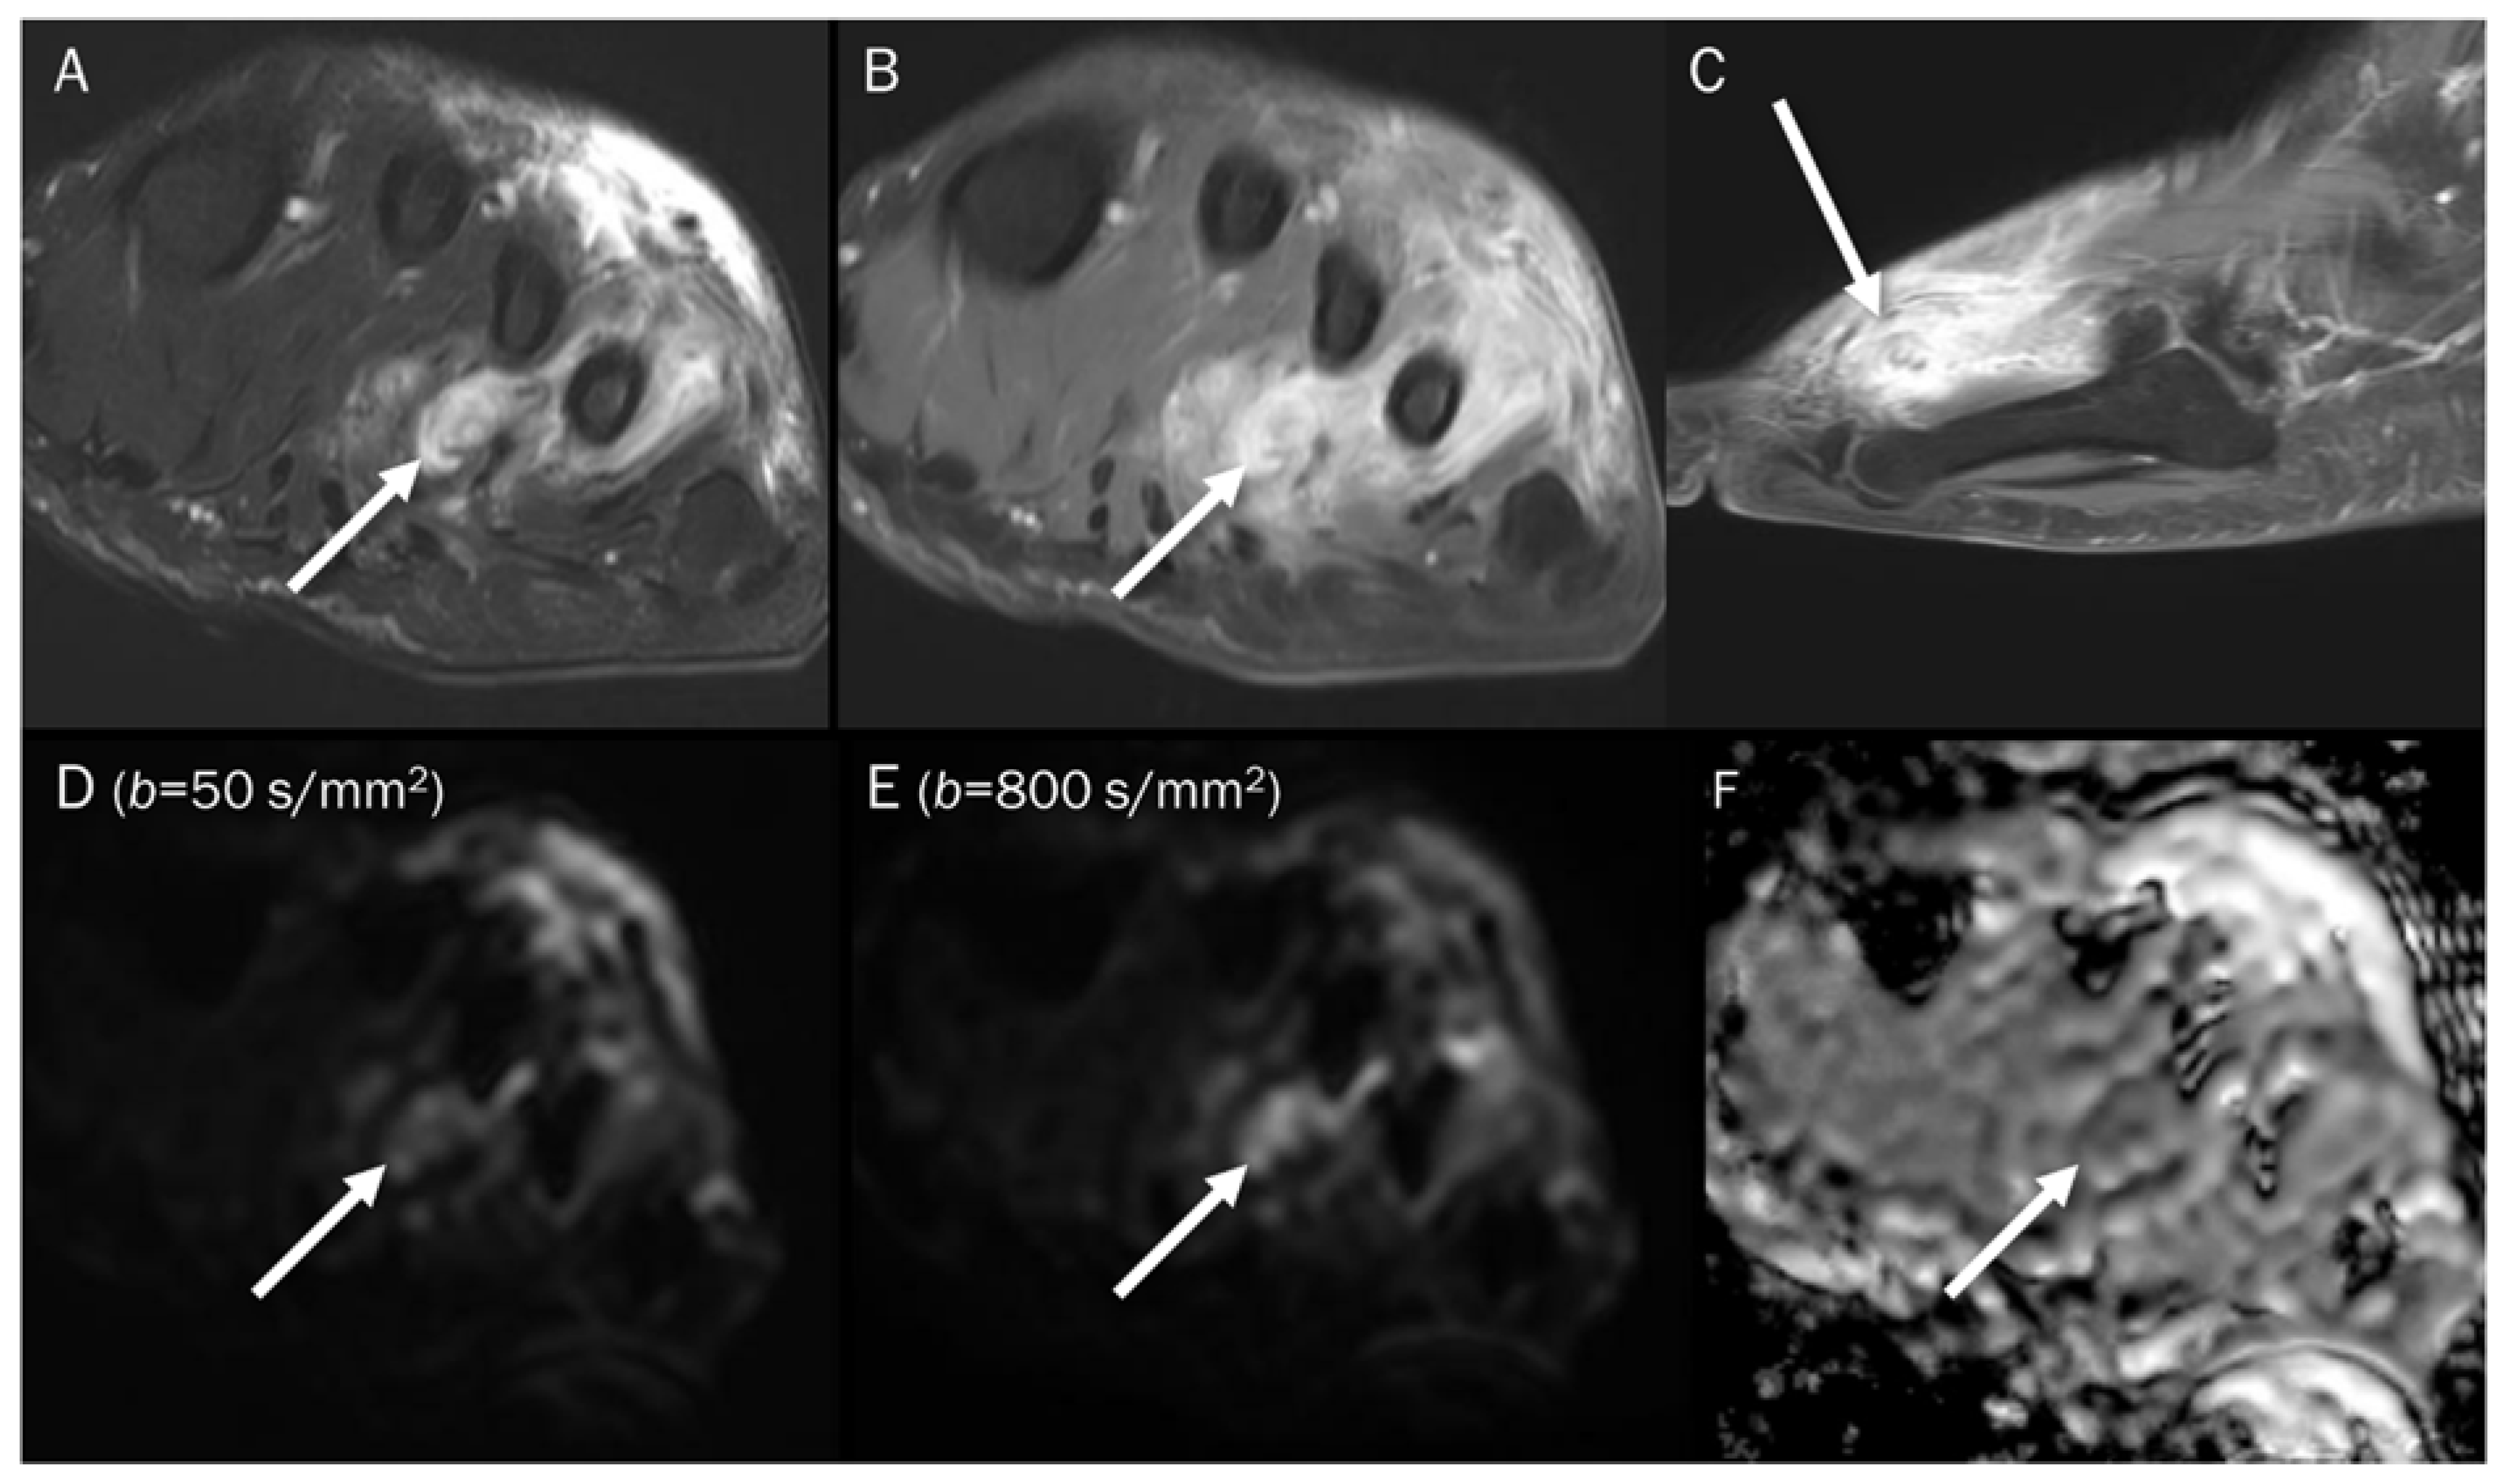

7.3. Benign Bone and Soft Tissue Tumors

| Non-ossifying fibroma | T2 black-out | Collagen fibers |

| Giant-cell tumor | T2 black-out | Hemosiderin |

| Gouty tophi | T2 black-out | Monosodium urate crystal |